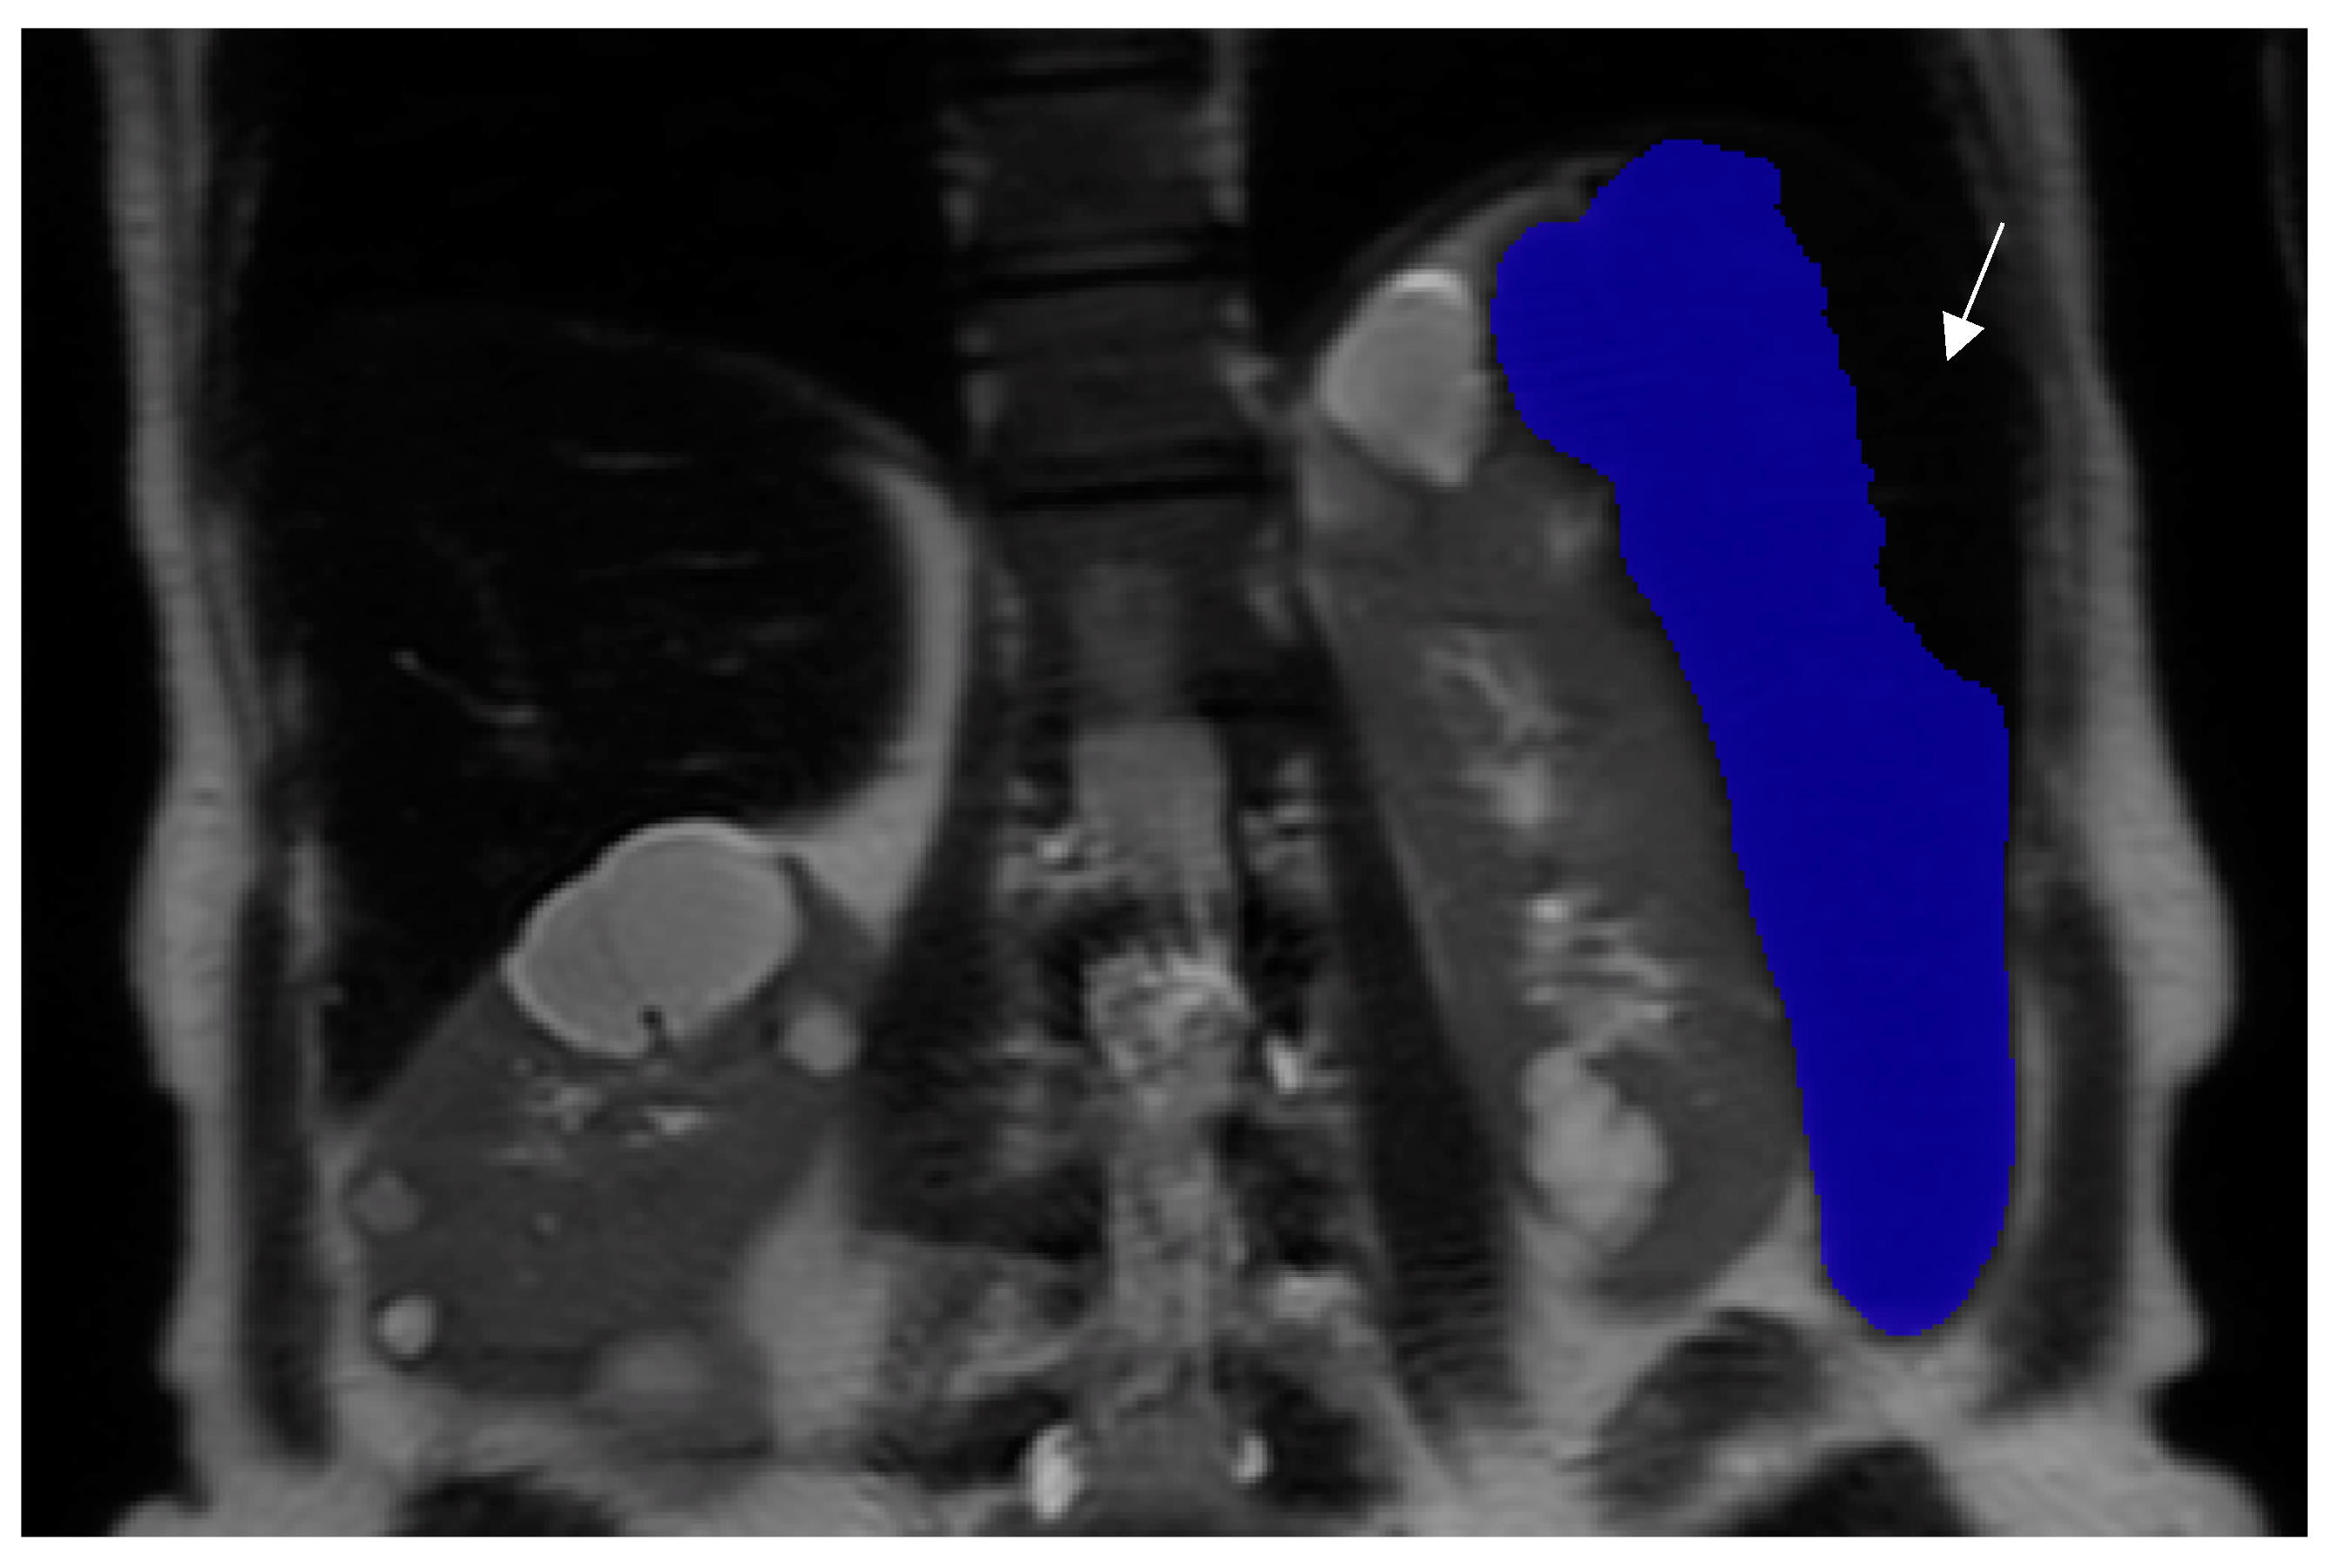

2.3. Deep Learning Model for Spleen Contouring

2.4. Spleen Volume Measurements